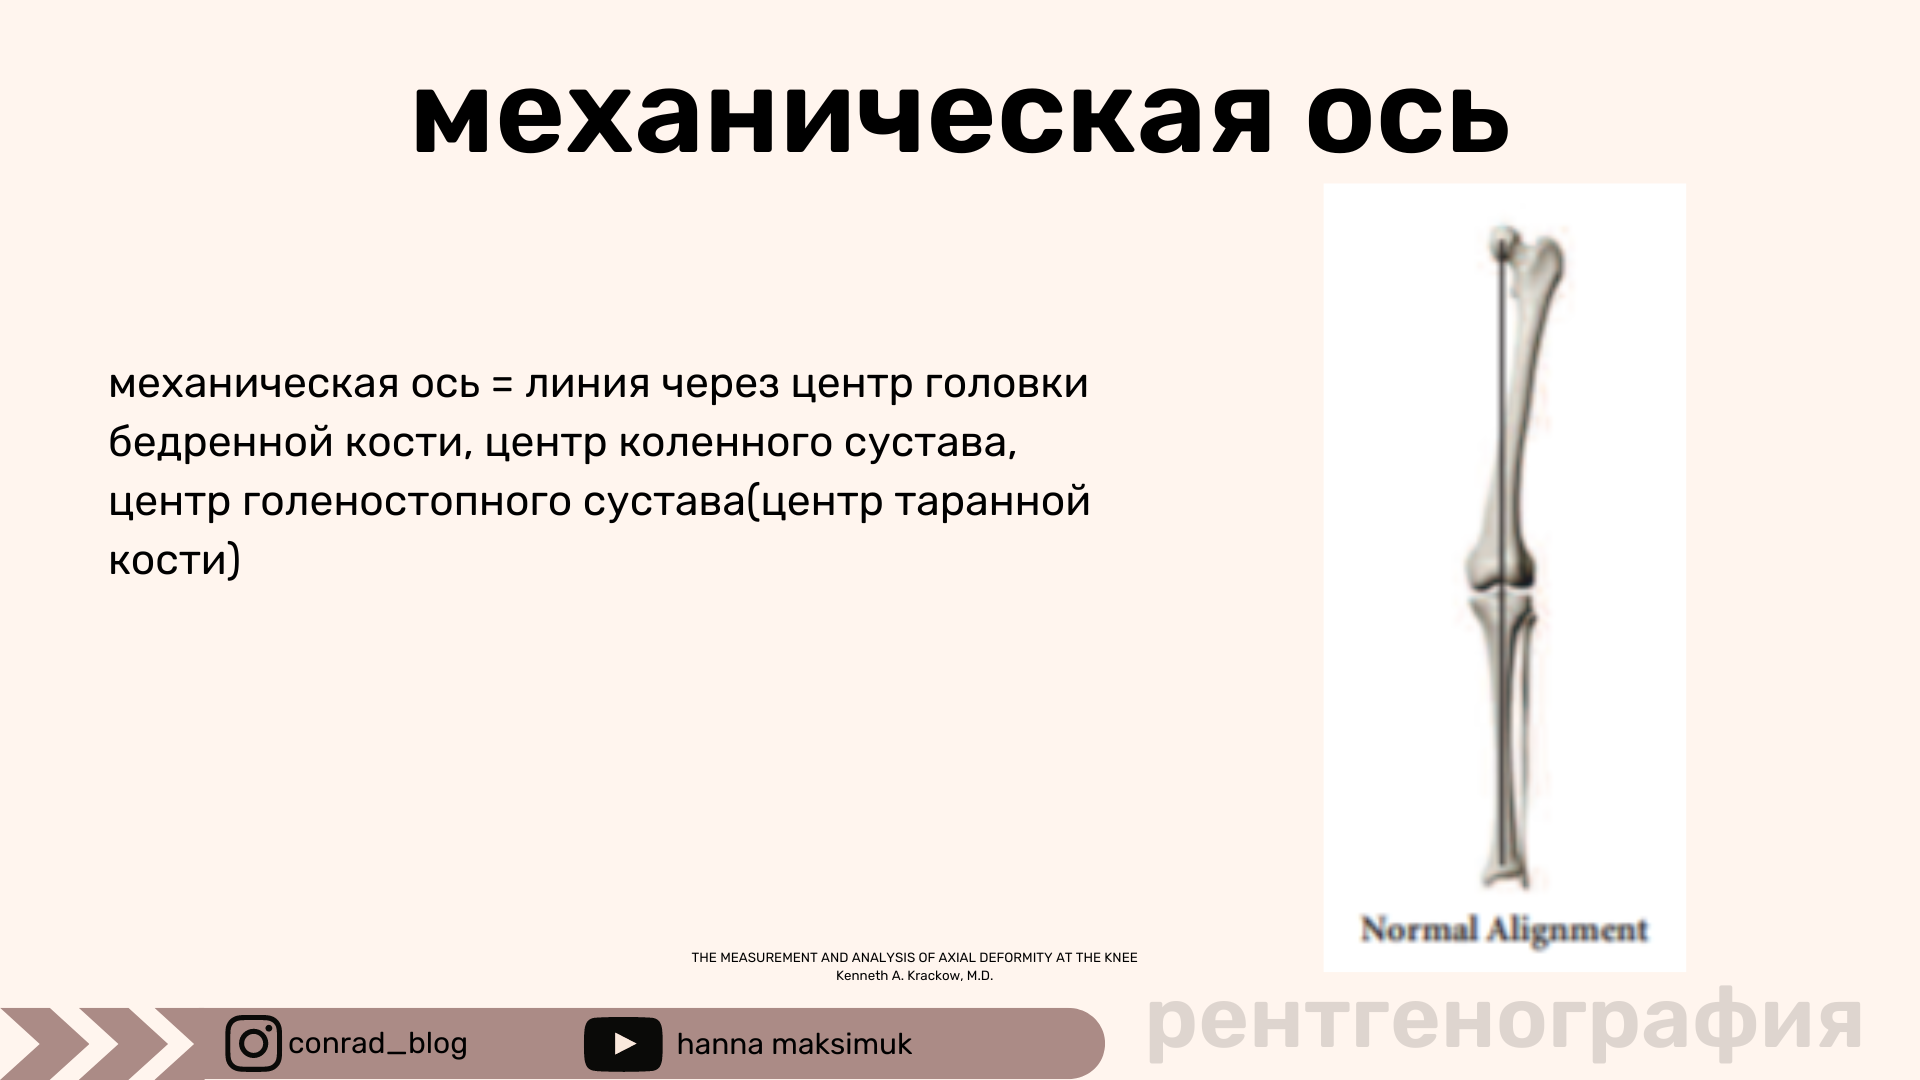

КОНСПЕКТА РАДИОЛОГА - 6 видео с теоретическим материалом